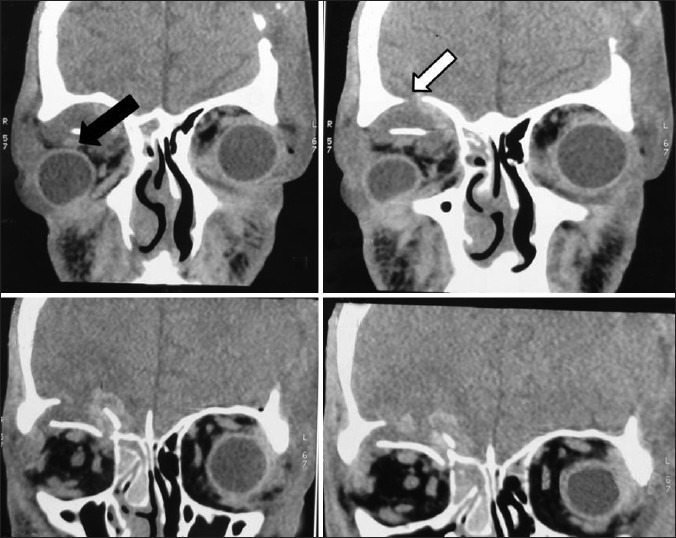

Spheno-orbital encephalocoele, due to dysplasia of the greater wing of the sphenoid is commonly seen in _____

Hint: inherited condition